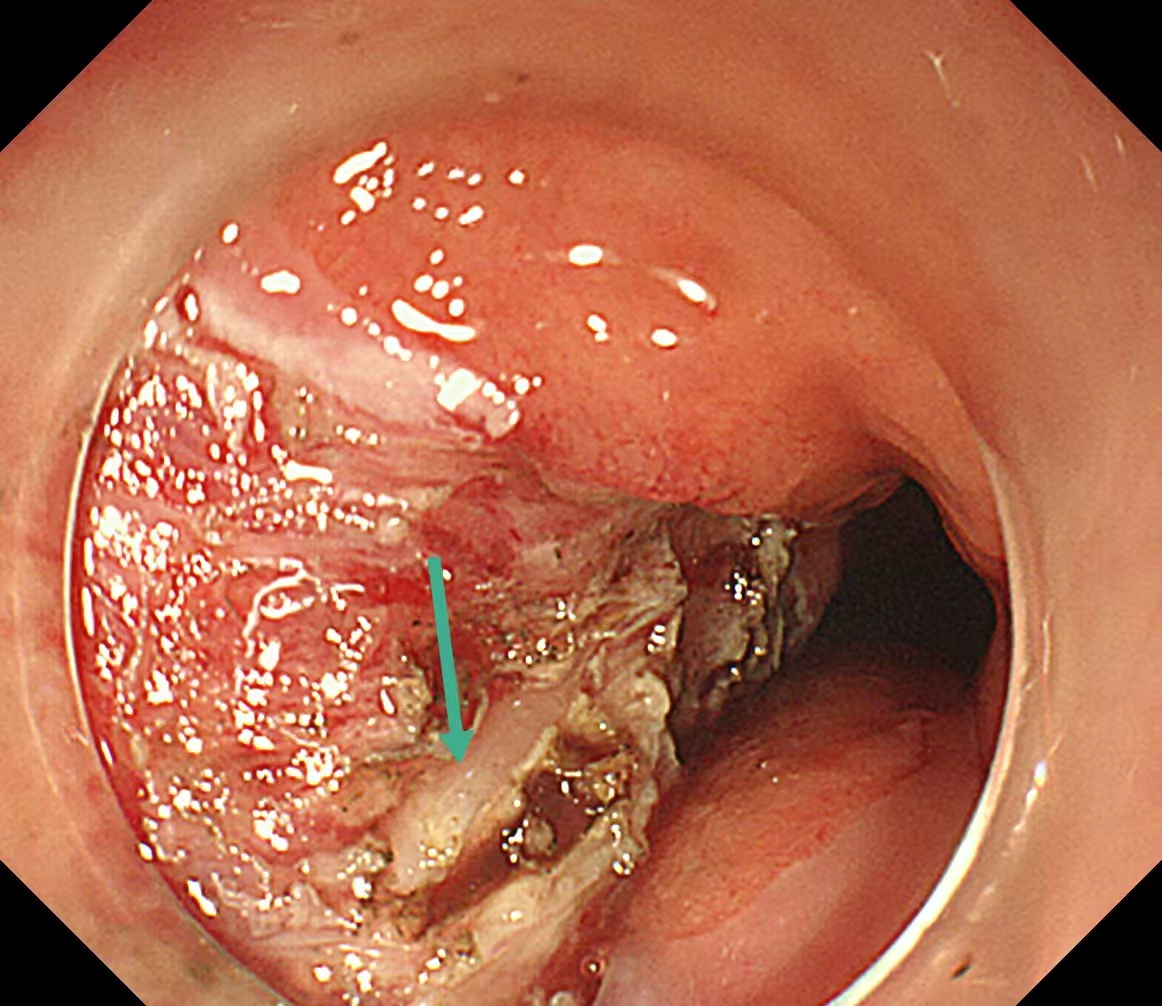

暴露出固有肌层,在肌层内寻找到异物

手术台上,刘蔚先小心翼翼切开脓肿处的食管黏膜,大量黄色脓液瞬间涌出,先为食管“排脓减压”;随后逐层探查,黏膜下层翻找无果,便屏住呼吸,在毫厘之间轻轻切开固有肌层,目光紧紧锁定视野,在与肌肉颜色近乎一致的地方,终于发现了那根“藏猫猫”的鱼刺!刘蔚轻夹鱼刺,慢慢提拉,生怕稍一用力刺破食管壁,这根长度1.5厘米的鱼刺,终于被成功取出,与CT报告完全吻合。